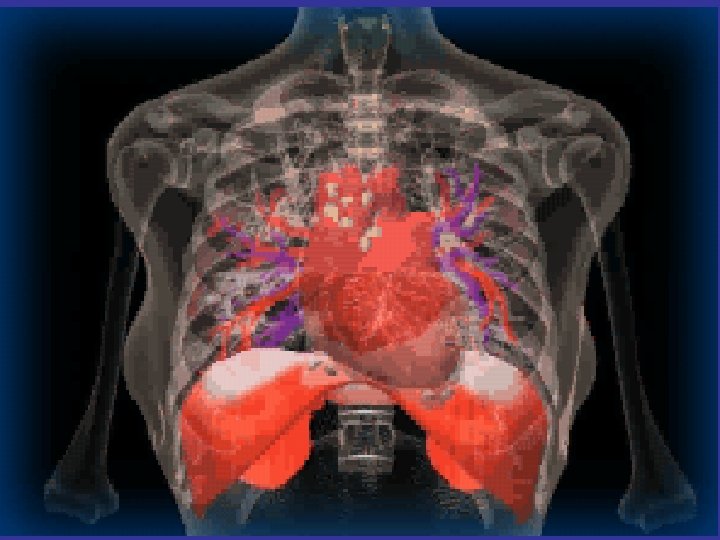

* trachea ; position & caliber * hila : lymphadenopathy * mediastinum contour : ? mass * heart : cardiac configuration Mediastinum, heart and hila

How to read a chest x ray ? • 1 - chest wall, bones and abdomen * bones; lesions or fractures * soft tissue ; mastectomy or soft tissue tumors • 2 - heart and mediastinum * trachea ; position & caliber * hila : lymphadenopathy * mediastinum contour : ? mass * heart : cardiac configuration • 3 - lungs opacity or lucency